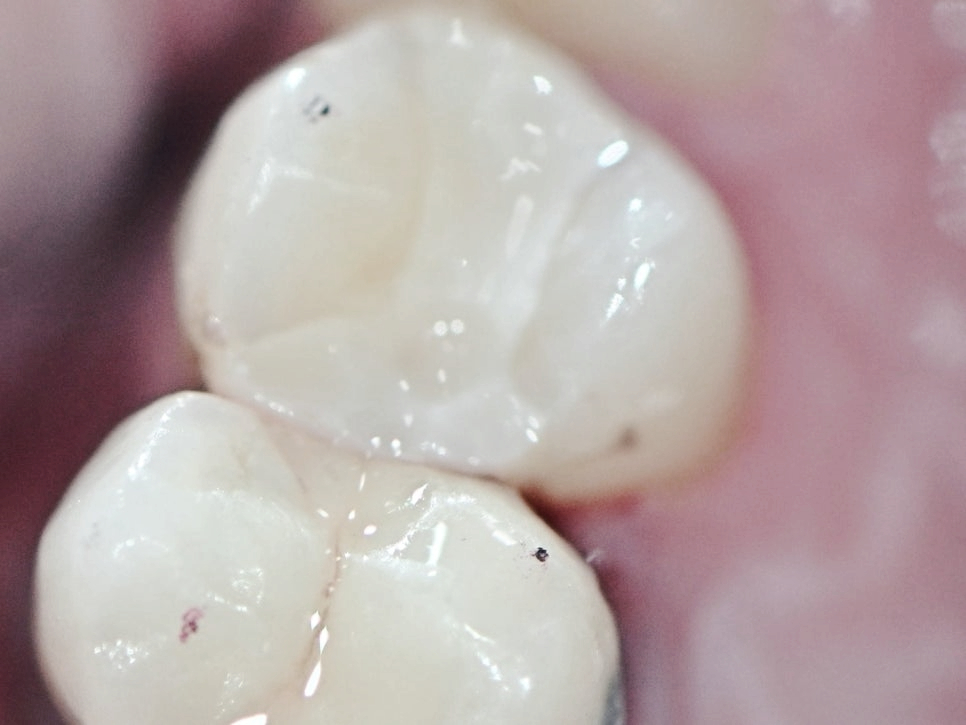

5단계. 최종 인레이 장착 & 교합 조정

마곡동치과_인레이 부착

드디어 제작된 인레이가 치과에 도착하면

임시 보철을 제거하고 정밀하게 인레이를 맞춰봅니다.

교합(씹는 힘의 균형)이 잘 맞는지, 치아 사이에 음식물이 낄 틈은 없는지,

접착 상태는 안정적인지 등을 꼼꼼히 체크한 뒤 최종 접착에 들어갑니다.

이후 마무리 광택 처리까지 완료되면,

진짜 ‘내 이빨 같은 느낌’의 인레이가 완성됩니다.